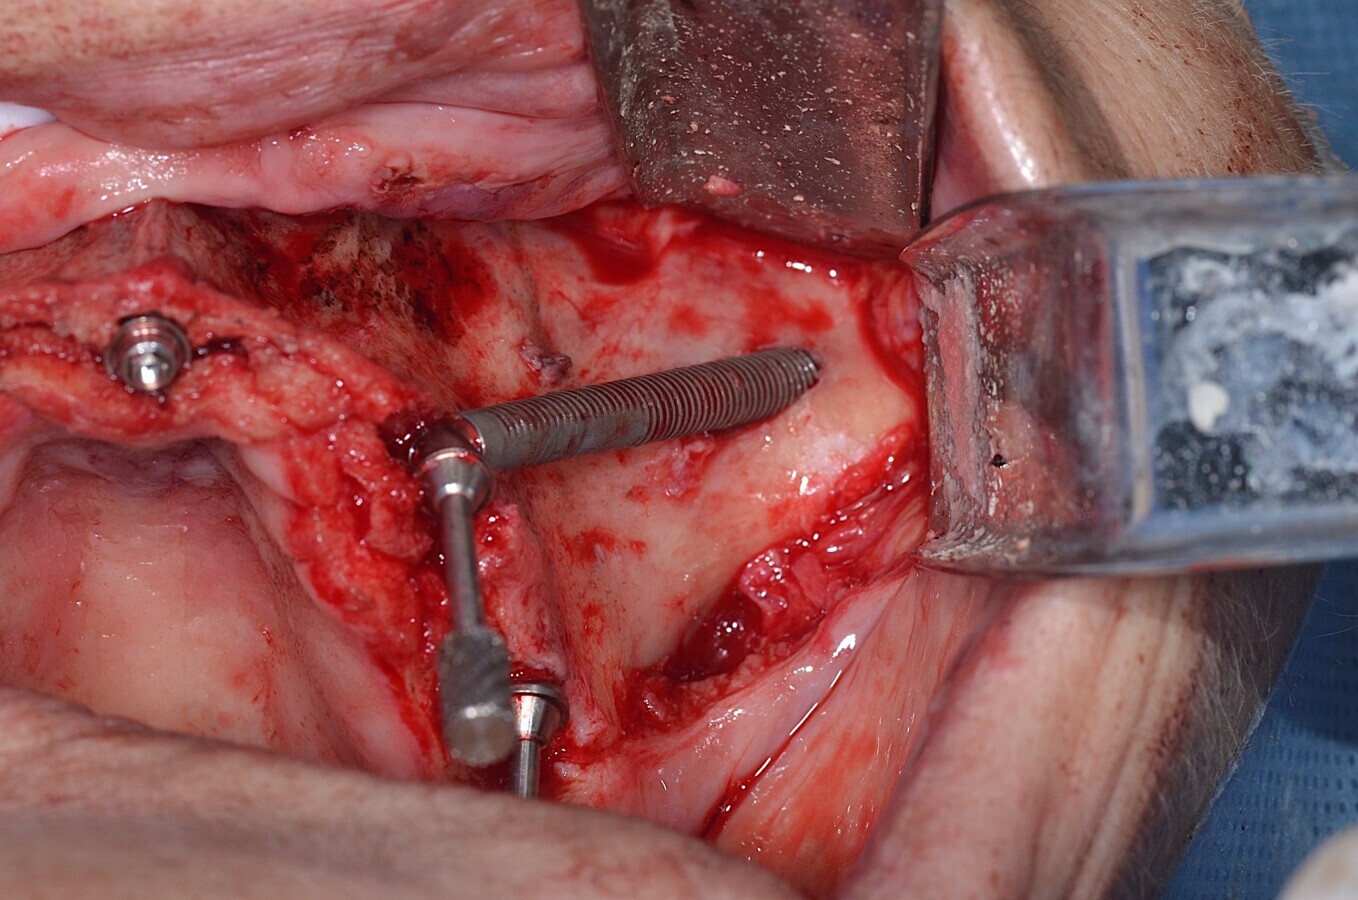

Figura 3. Aspecto intraoral del implante Zygoma GM colocado.

Bajo sedación endovenosa administrada por un anestesista, además de anestesia infiltrativa maxilar, se realizó un colgajo supraóseo de espesor completo con dos descargas posteriores para exponer el maxilar y el hueso cigomático, además del vaciamiento del conducto nasopalatino mediante electrocauterio. Se insertó la guía quirúrgica para orientar la perforación inicial de los implantes GM Zygoma según el protocolo de Neodent y la marcación ósea para la inclinación de los implantes GM Helix Acqua en la posición posterior, utilizando el protocolo de perforación reducida de Neodent con el protocolo de perforación del implante GM Helix Acqua ubicado en el área del nasopalatino. Se instalaron cinco implantes Neodent alcanzando torques de 50+ Ncm para cada implante. Luego se utilizaron el Mini Conical Abutment GM de 30° en los implantes posteriores, el Mini Conical Abutment GM de 45° para los implantes GM Zygoma y el Mini Conical Abutment GM para el implante nasopalatino, además del Temporary Abutment GM para el puente. Luego se cerró el sitio quirúrgico para la carga inmediata con el diseño de la prótesis impresa en 3D utilizando la bandeja de impresión multifuncional.